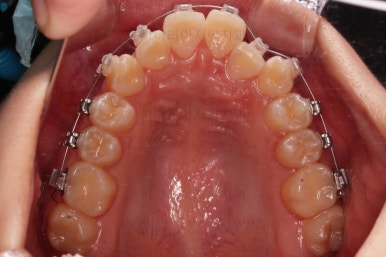

치료 종료시의 모습이에요.

총 21개월 걸렸고요.

발치를 중간에 결정했기 때문에 조금 지체된 면이 없지 않았으나 기간부터 치료 결과까지 만족스러운 치료였습니다.

치여링 가지런해졌고, 교합과 중앙선 등 입안의 모습이 매우 좋아졌어요.

불규칙하게 마모되어 있던 치아의 개별 형태도 약간씩 다듬어 드렸고요.